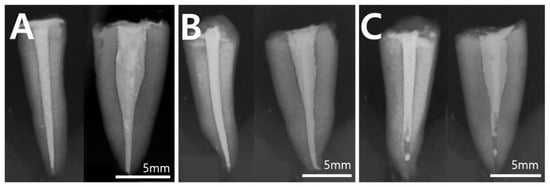

2.3. Radiographic Evaluation for Canal Obturation

- MTA using the monoblock obturation group revealed root filling with voids on post-obturation radiography. Its fracture resistance was lowest among the filled groups, although the difference was insignificant.